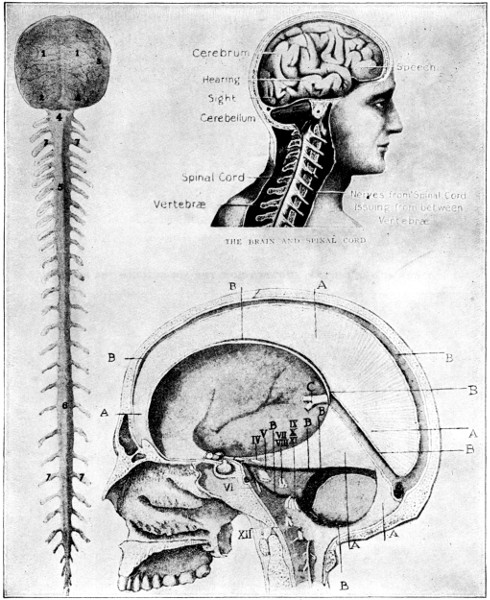

ITS STRUCTURE—ORGANIZATION INTO SYSTEMS—FUNCTIONS—SPECIAL SENSES—NERVOUS SYSTEM—PERSONAL HYGIENE—PREVENTION OF DISEASE—INTERDEPENDENCE OF BODY AND MIND—EUGENICS—ILLUSTRATIONS AND CHARTS.